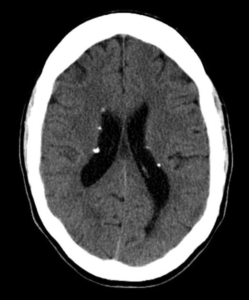

4) با توجه به عدم تمایل خانواده برای انجام ام آر آی تحت بیهوشی، جهت شیرخوار سی تی اسکن مغز بدون تزریق انجام می شود:

یافته فوق را توصیف کنید.

| گزینه | بازخورد | نمره انتخاب | عدم انتخاب | مرگ | |

| یافته فوق در شیرخواران واریاسیون نرمال است. | یافته فوق در شیرخواران واریاسیون نرمال است. | -2.00 | 0.00 | ||

| Germinal matrix hemorrhage مطرح است. | Germinal matrix hemorrhage مطرح است. | -1.00 | 0.00 | ||

| Brain stone مشهود است. | Brain stone مشهود است. | 2.00 | 0.00 | ||

| Tram Track sign دوطرفه دارد. | Tram Track sign دوطرفه دارد. | -1.00 | 0.00 | ||

| سی تی اسکن بیمار به نفع هیپرپاراتیروییدی است. | سی تی اسکن بیمار به نفع هیپرپاراتیروییدی است. | -1.00 | 0.00 | ||

| یافته مشابه در fahr disease مشهود است. | یافته مشابه در fahr disease مشهود است. | -1.00 | 0.00 |